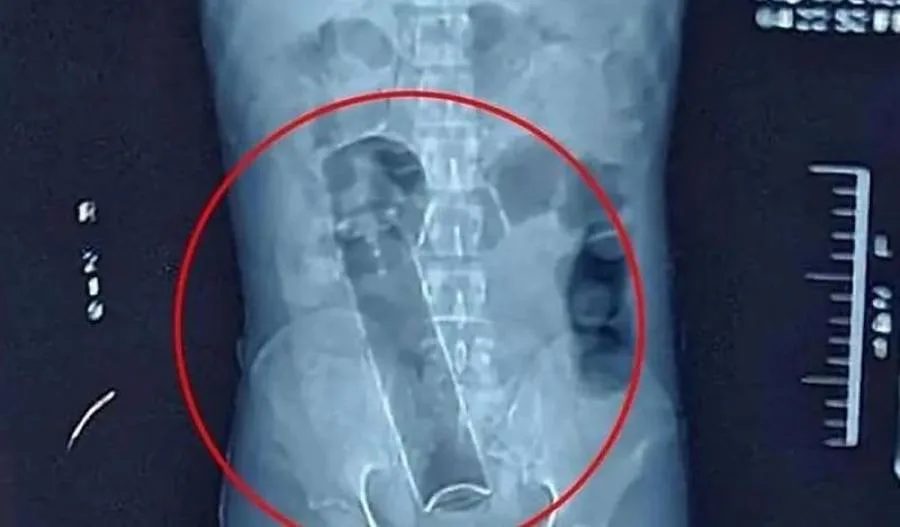

No local, a equipe médica realizou avaliação clínica e radiológica para identificar a posição do objeto, conforme protocolo adotado em casos de corpo estranho retal. O desodorante, então, foi removido com procedimento médico específico, sem precisão de intervenção cirúrgica.